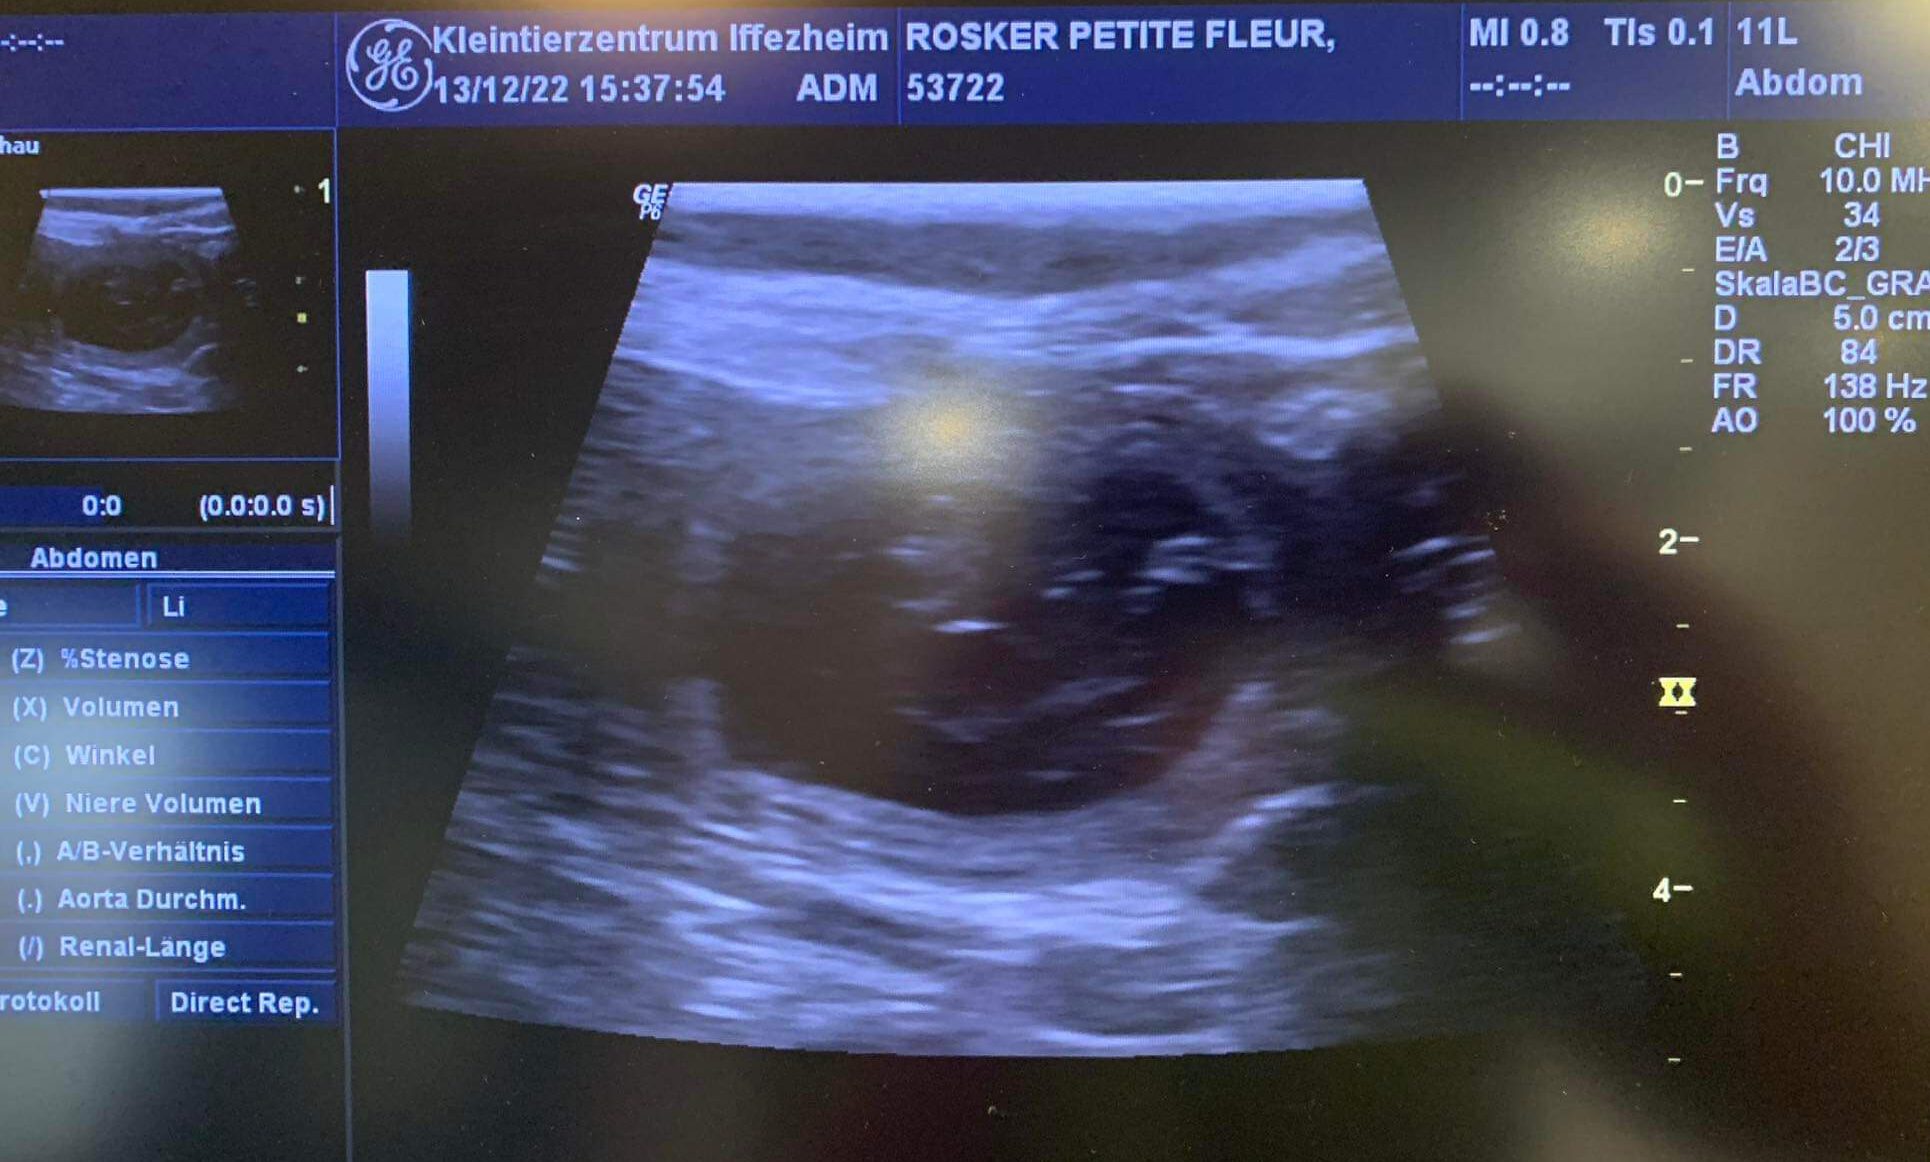

Braune und schwarze Welpen werden erwartet. 14. Dezember 2022KommentarnavigationZurückVorheriger Beitrag:W-Wurf hat am 2.12 das Licht der Welt erblicktNächstesNächster Beitrag:Der X-Wurf wurde am 18.01.2023 geborenÄhnliche BeiträgeDer Ultraschall hat bestätigt: wir erwarten den D2-Wurf nach Ostern4. März 2026Vivi wurde am 5.2 von Jake (Plainfire‘s I‘m On Fire) gedeckt.9. Februar 2026Vivi ist läufig und soll Anfang Februar gedeckt werden26. Januar 2026